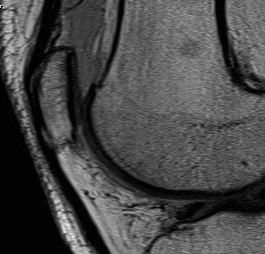

MRI

Osteochondral Fragment in PFJ